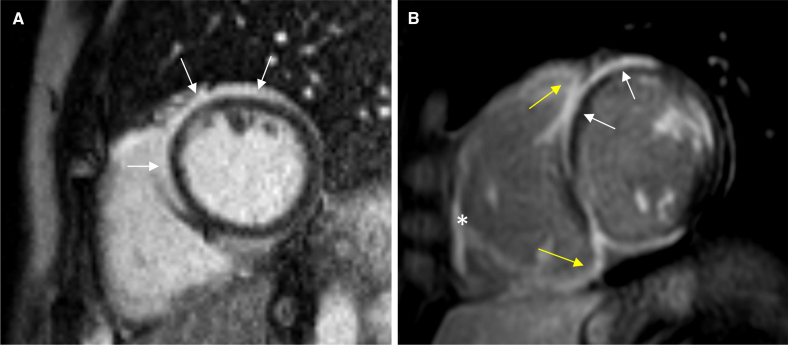

Background: Cardiac sarcoidosis involves a significant but difficult-to-define risk of sudden cardiac death (SCD). Current guidelines recommend consideration of an implantable cardioverter defibrillator for patients with extensive or significant myocardial late gadolinium enhancement (LGE) on cardiac magnetic resonance imaging. However, extensive/significant LGE is not defined.

Methods: A nationwide cardiac sarcoidosis registry was screened for patients entered before 2020 with cardiac magnetic resonance imaging done before or <3 months after diagnosis. Available studies were re-analyzed for LGE mass as a percentage of left ventricular (LV) mass and the number of LGE-positive LV segments in a 17-segment model. The occurrence of fatal or aborted SCD and ventricular tachycardia (VT) prompting therapy was recorded until the end of 2020 and subjected to cumulative incidence analyses, including competing events (LV assist device implantations, heart transplantations, and fatalities other than SCD). The predictors of SCD/VT were assessed using Fine and Gray modeling and time-dependent receiver operating characteristic analysis.

Results: Altogether, 305 patients (66% women, median age 51) with clinically manifest, definite (45%) or probable cardiac sarcoidosis (55%) were analyzed. On follow-up (median, 4.0 years), 21 SCDs, 60 VTs, and 14 competing events were noted. Both LGE mass and the number of LGE segments predicted the composite of SCD/VT (P<0.001), with receiver operating characteristic analyses identifying LGE mass ≥9.9% and ≥6 LGE segments as discriminative thresholds. At presentation, 70 patients were free of class I and class IIa implantable cardioverter defibrillator indications unrelated to LGE. Their 5-year rate of SCD/VT was 6.3% (0.0-14.8%) with LGE mass <9.9% versus 21.5% (6.5-36.6%) with higher LGE mass, and 6.9% (0.0-16.3%) with <6 LGE segments versus 20.5% (5.9-35.2%) with ≥6 segments.

Conclusions: In cardiac sarcoidosis, myocardial LGE making up ≥9.9% of LV mass or affecting ≥6 LV segments may suggest prognostically significant LV involvement and a high risk of SCD. However, prospective validation of the thresholds is needed.